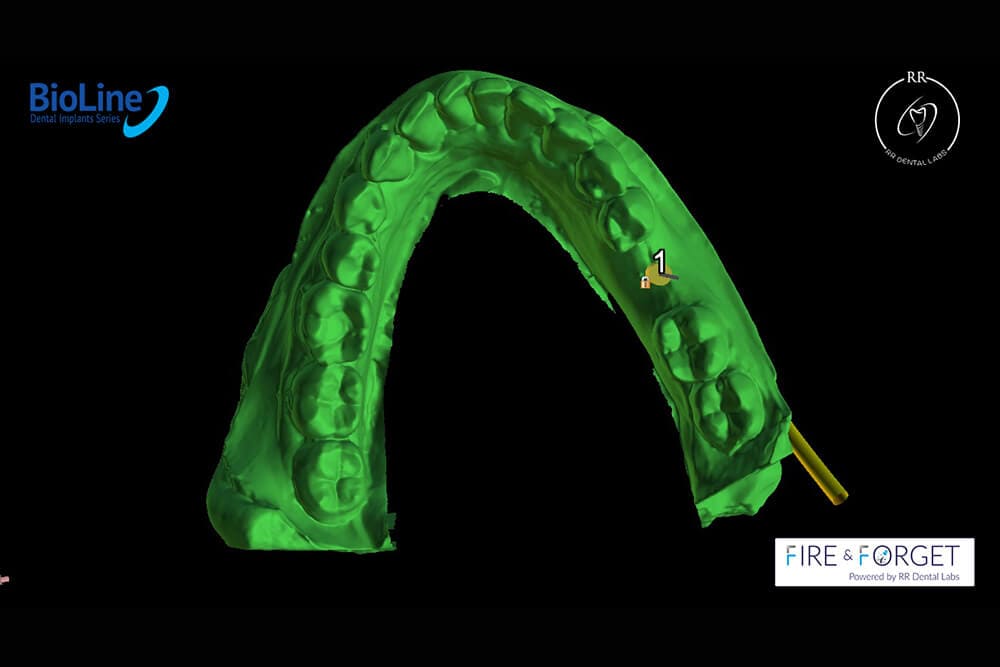

Case 26